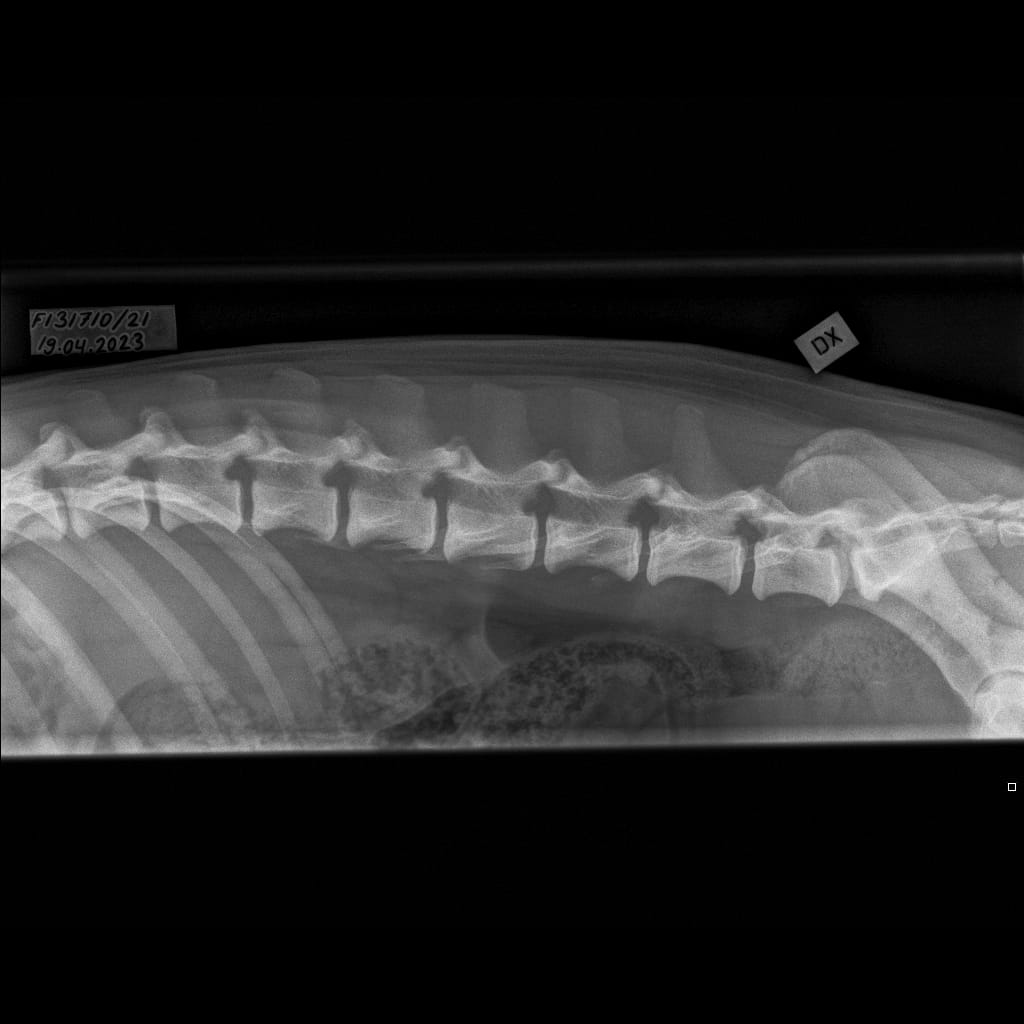

| Spine: | LTV0, SP0, VA0 | ||

| Spine: | LTV3, SP0, VA0 | ||

| Spine: | LTV1, SP0, VA1 |

| Spine: | LTV2, SP0, VA0 |

| Spine: | LTV0, SP0, VA0 |

| Spine: | LTV1, SP0, VA0 |